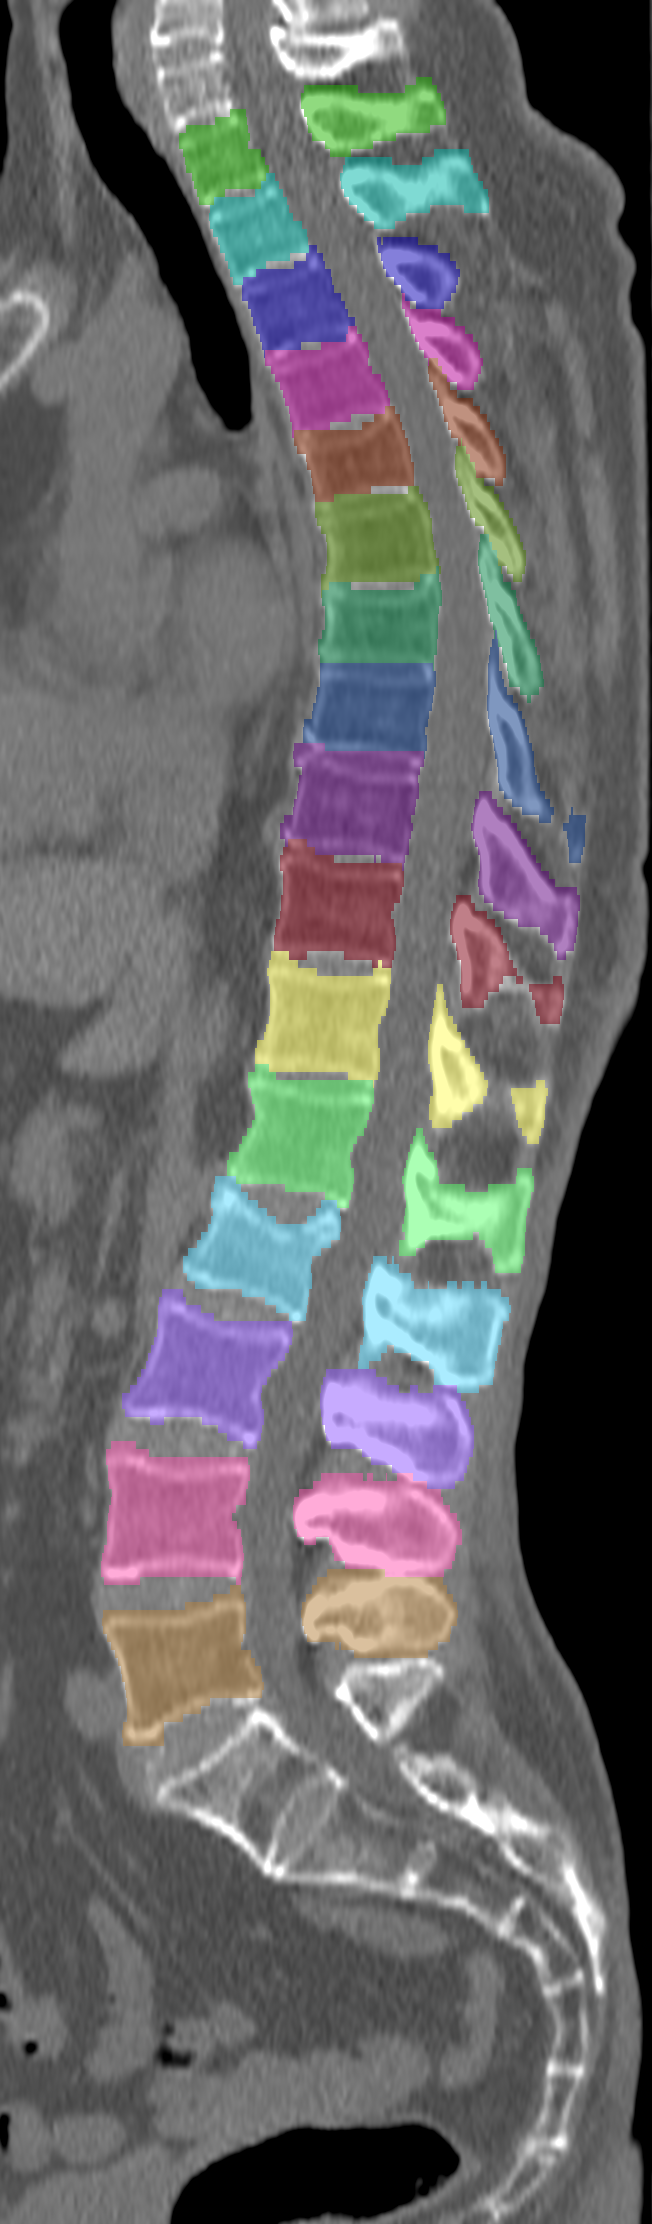

Normalized CT images and reference segmentations of thoracic and lumbar vertebrae from the CSI 2014 workshop

This is the dataset of the vertebra segmentation challenge of the CSI 2014 workshop that was held in conjunction with MICCAI 2014.

- Vertebrae have been anatomically labeled (8 = T1, 9 = T2, ..., 24 = L5)

- Because not always all visible vertebrae were segmented in the original data, only segmentations of the thoracic and lumbar vertebrae have been retained